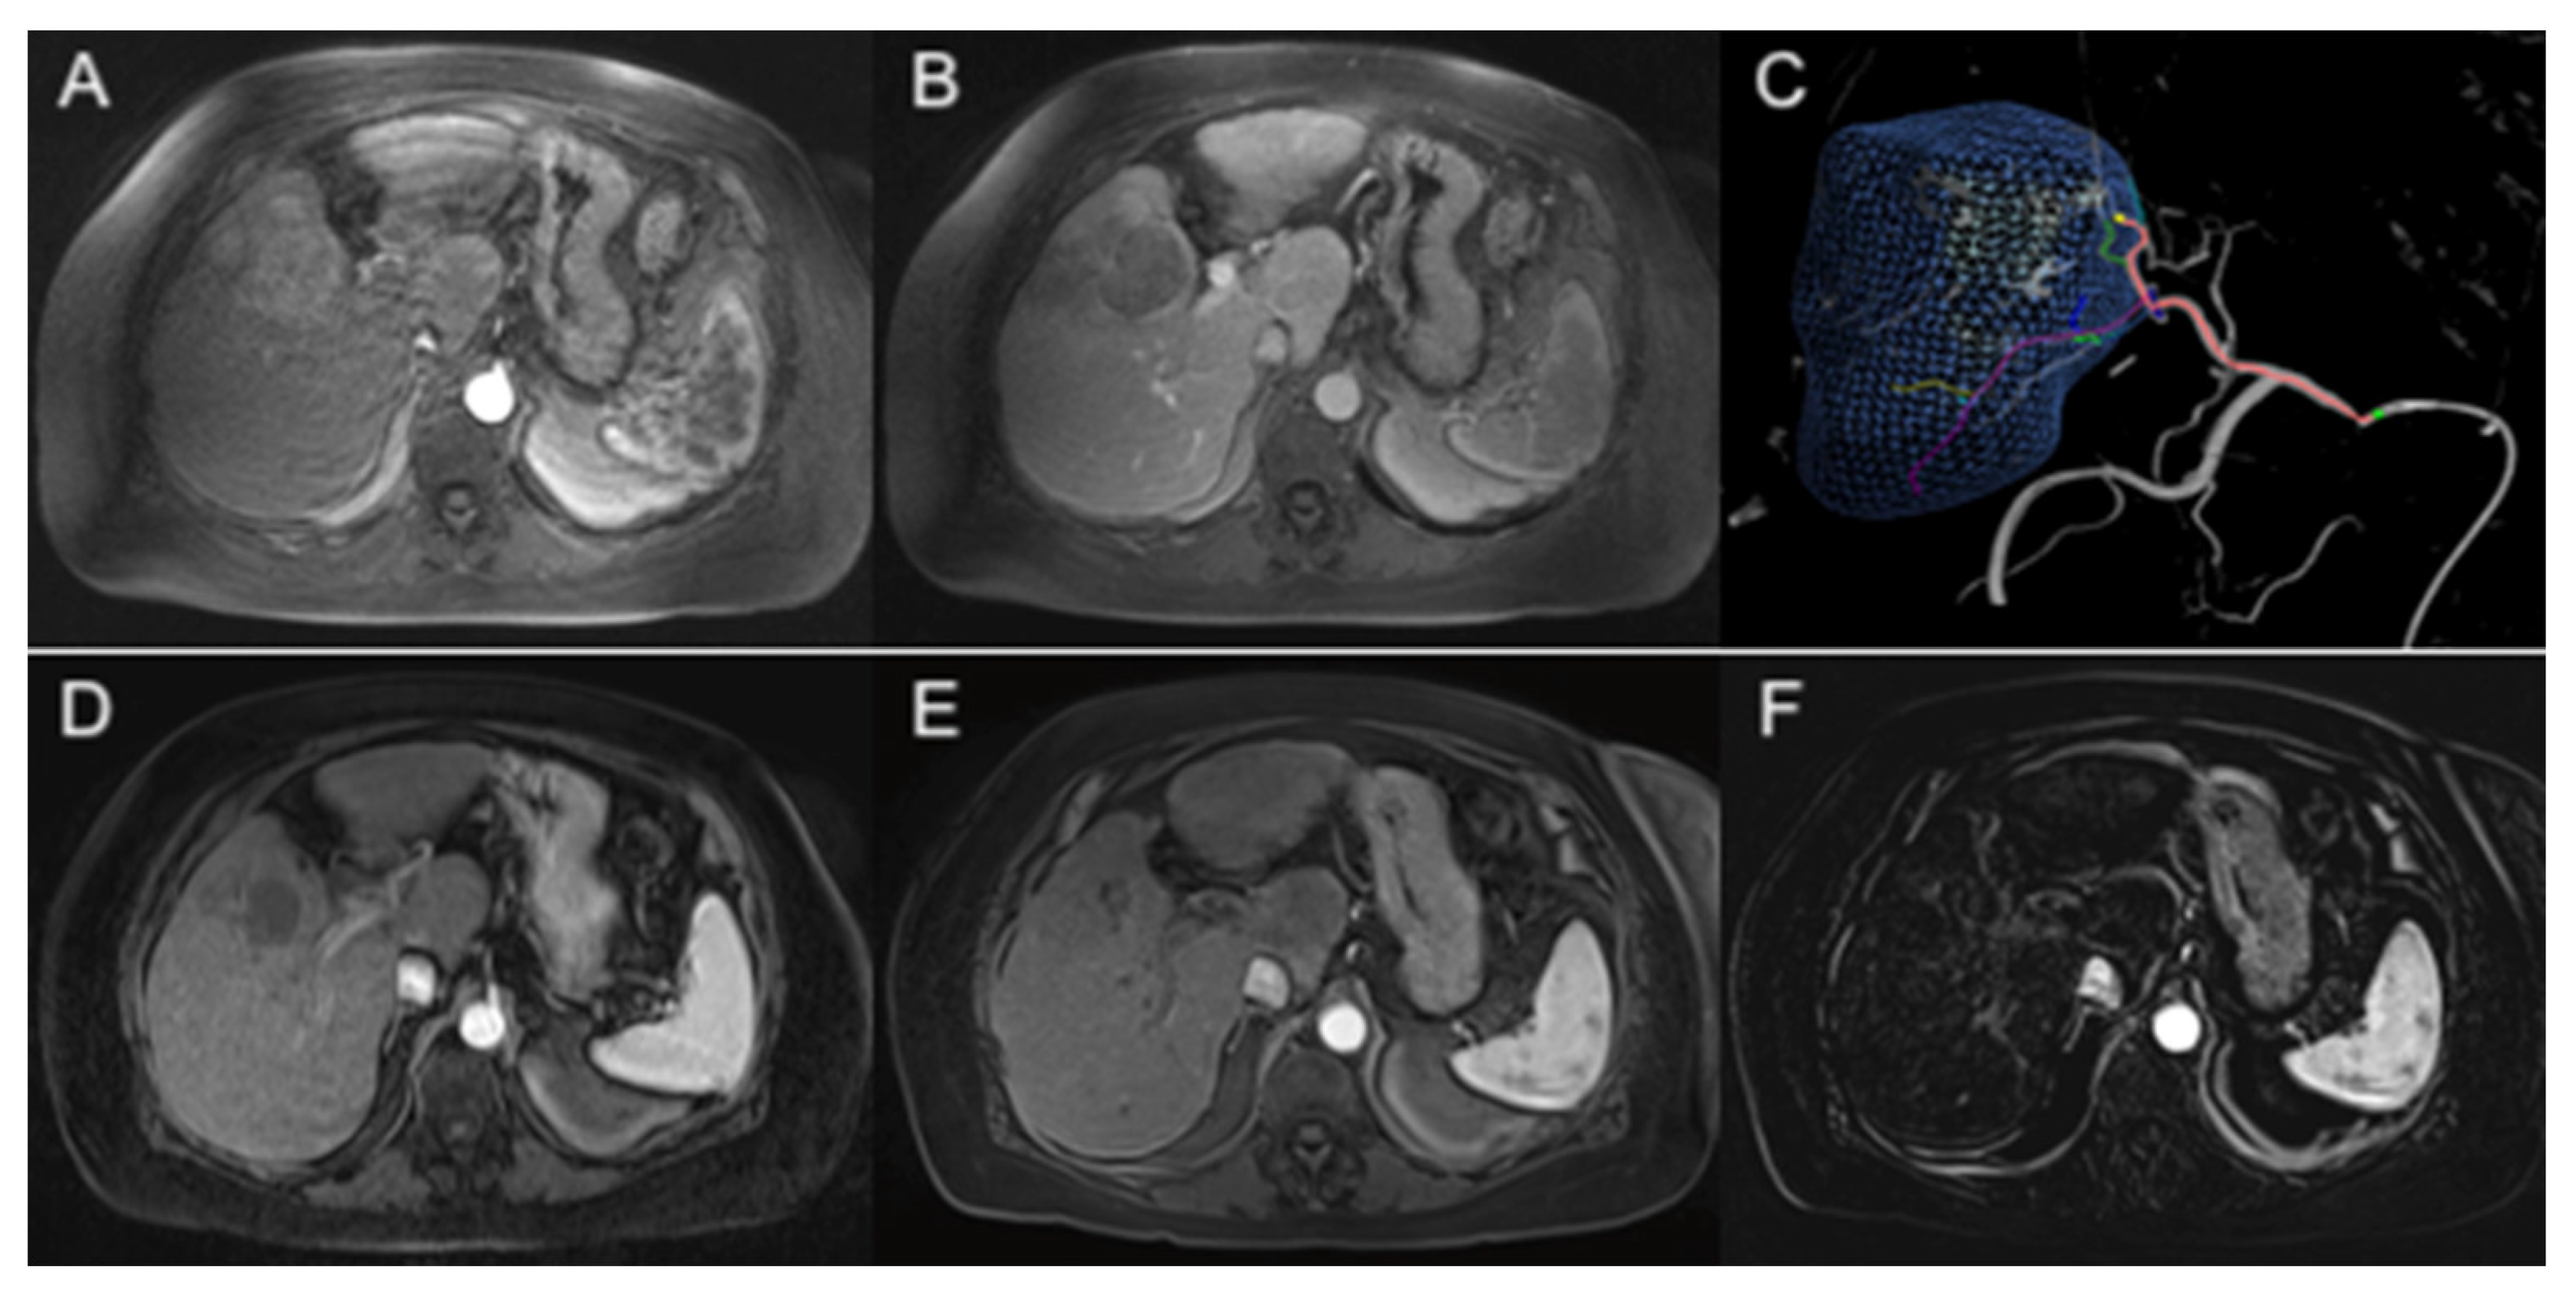

- Abi-Jaoudeh, N.; Dayyani, F.; Chen, P.J.; Fernando, D.; Fidelman, N.; Javan, H.; Liang, P.-C.; Hwang, J.-I.; Imagawa, D.K. Phase I Trial on Arterial Embolization with Hypoxia Activated Tirapazamine for Unresectable Hepatocellular Carcinoma. J. Hepatocell. Carcinoma 2021, 8, 421–434. [Google Scholar] [CrossRef]

- Liu, C.-H.; Peng, C.-M.; Hwang, J.-I.; Liang, P.-C.; Chen, P.-J.; Abi-Jaoudeh, N.; Giiang, L.-H.; Tyan, Y.-S. Phase I Dose-Escalation Study of Tirapazamine Chemoembolization for Unresectable Early- and Intermediate-Stage Hepatocellular Carcinoma. J. Vasc. Interv. Radiol. 2022, 33, 926–933.e1. [Google Scholar] [CrossRef]